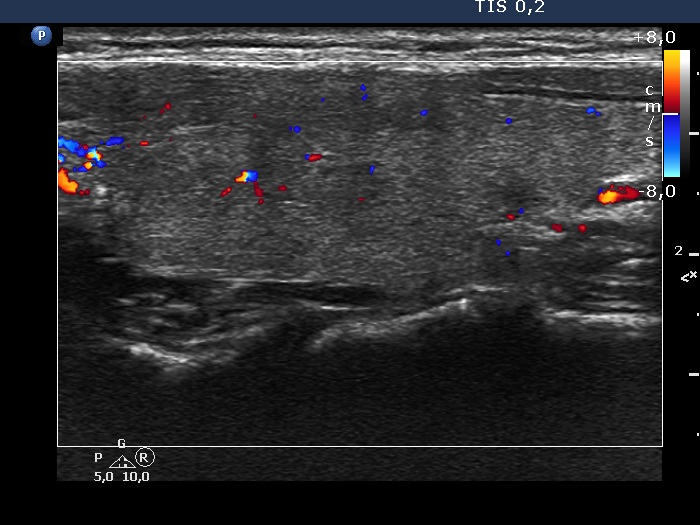

Two years after the first visit (second row of images):

Clinical presentation: The patient requested evaluation of neck complaints. Her left thyroid became painful and she became feverish 3 weeks ago. She suffered from upper airways infection 2.5 months before the onset of complaints.

Palpation: Both lobes became hard. The right lobe was very sensitive while the left was painful on palpation.

Laboratory tests: TSH 0.02 mIU/L, FT4 30.7 pM/L, CRP 51.8 mg/L.

Ultrasonography: The thyroid became minimally hypoechoic and more hypoechoic areas have appeared in both lobes. The echogenicity index was 20% and 50%, right and left lobe, respectively. The vascularity was decreased.

Suggestion. Steroid therapy.